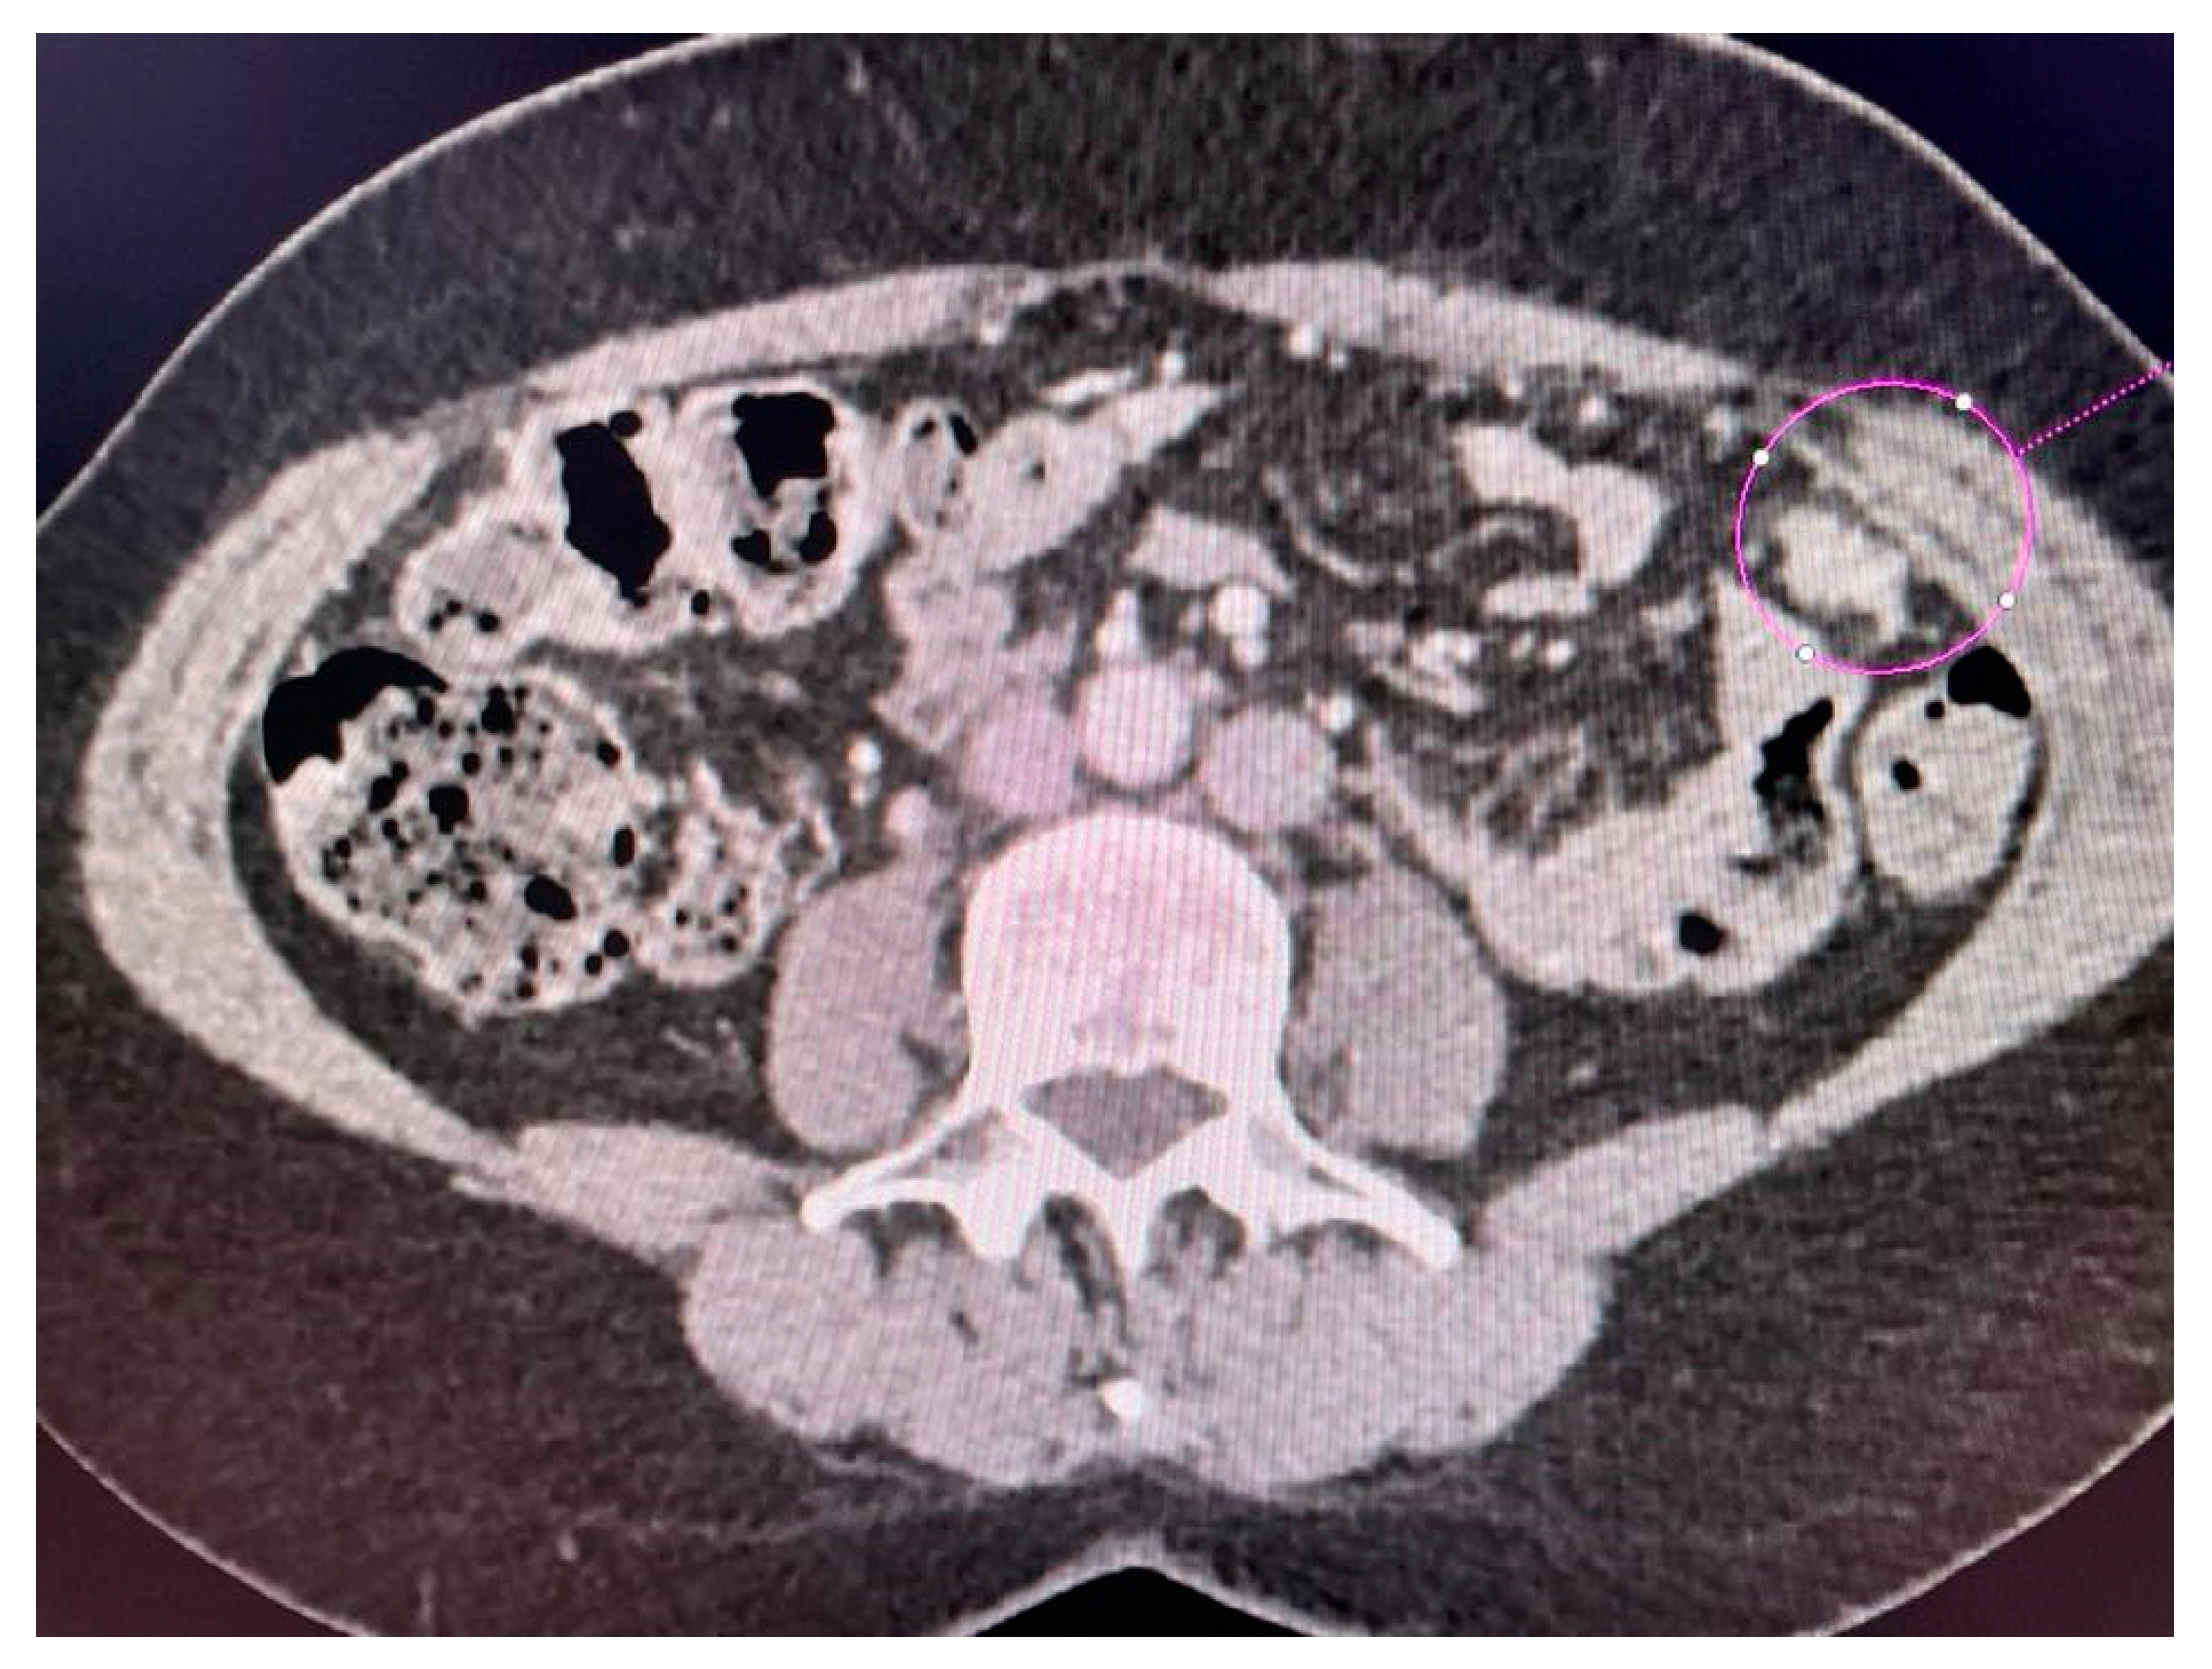

2.3. Computed Tomography Examination